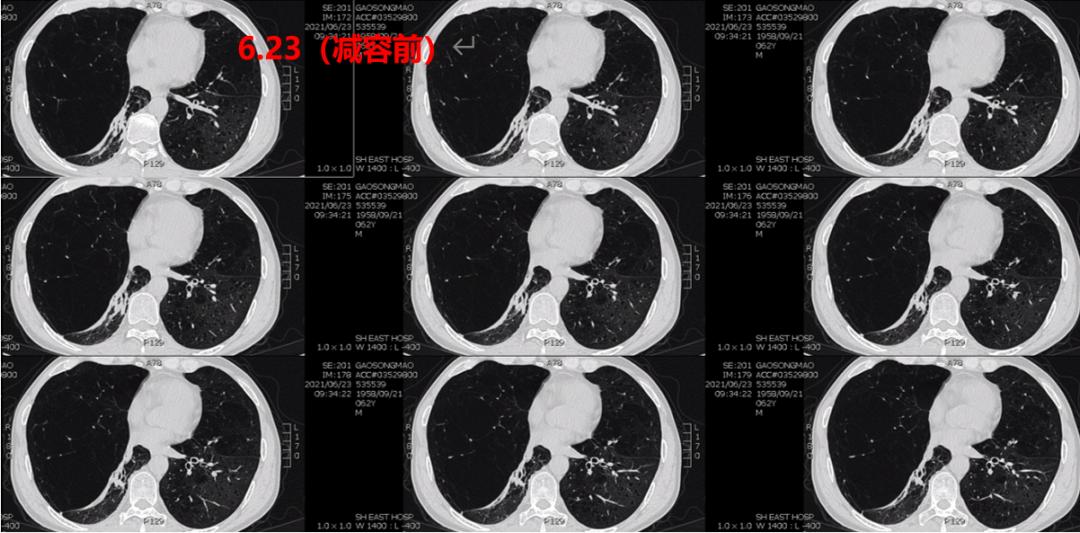

2021.06.23 胸部CT平扫:1.肺气肿,肺大疱;右肺中叶巨大肺大疱伴部分肺组织膨胀不全;2.两肺上叶陈旧灶,两肺少许纤维灶;3.主动脉钙化。

图2-4入院后完善相关检查,于2021.06.25行全麻下胸腔镜下肺大疱减容术(右侧),术后予以镇痛、抗感染、止咳平喘、经鼻高流量氧疗(HFNC)等治疗。